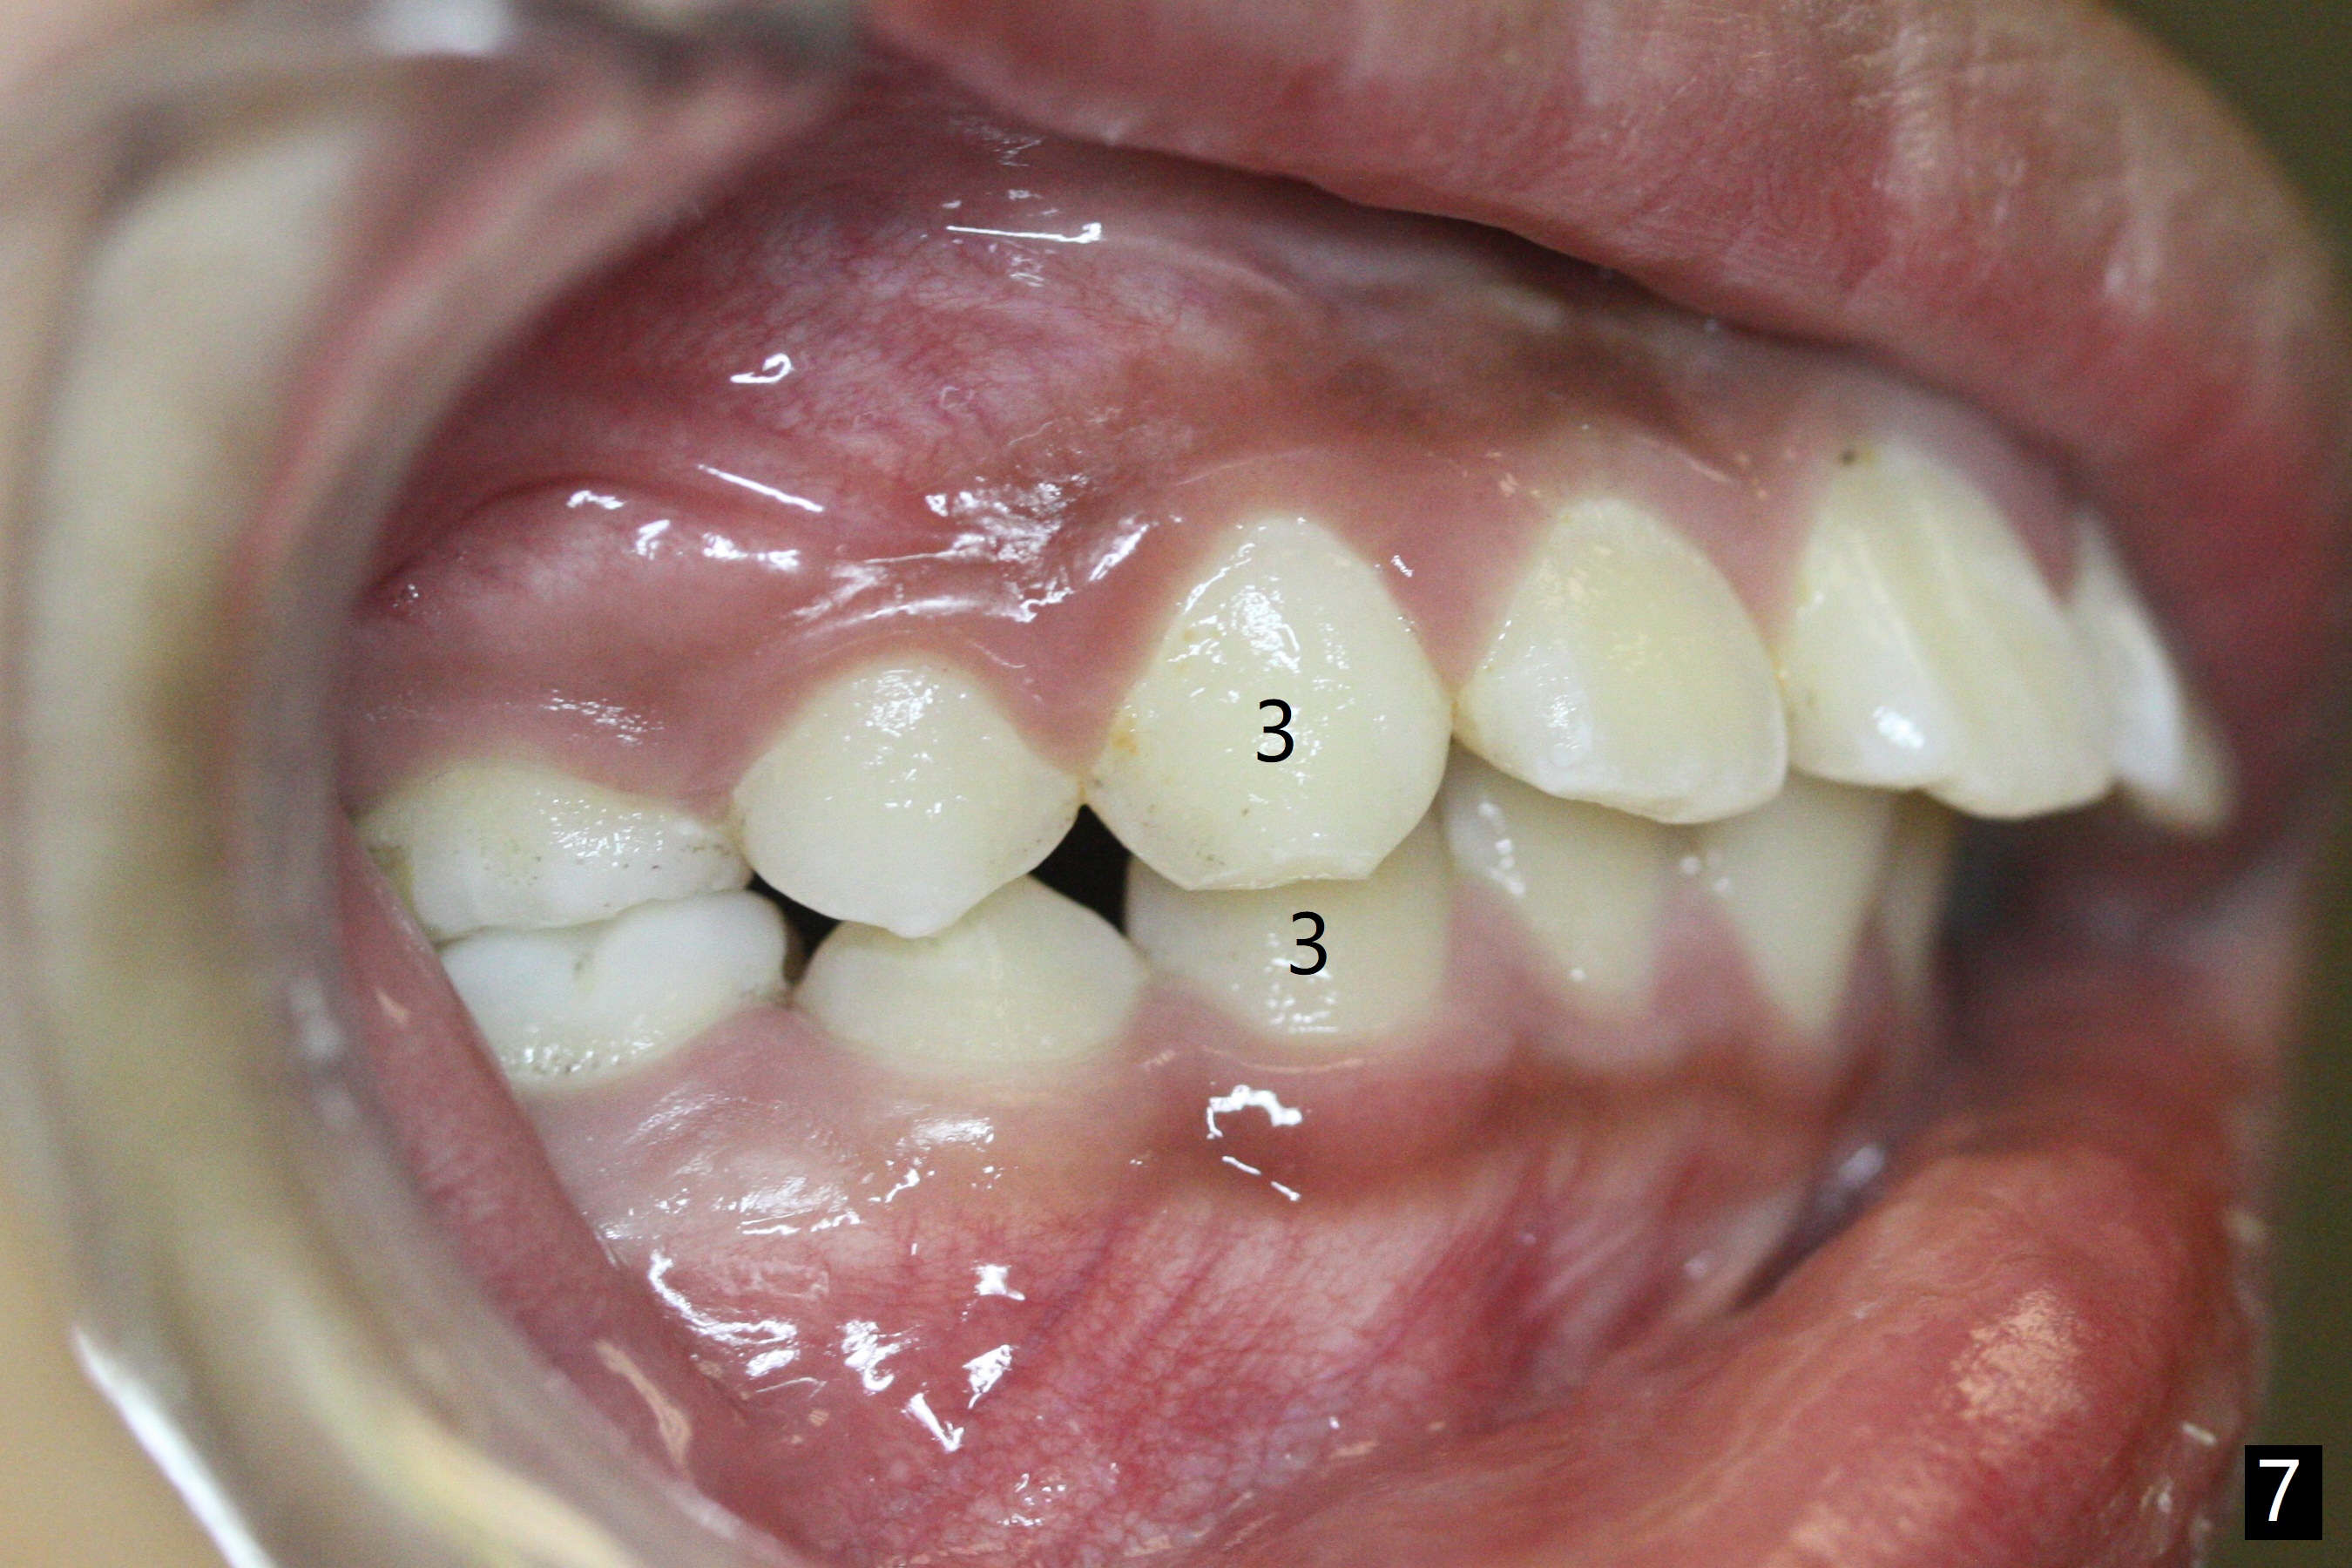

The mother of a 10-year-7-month old man requests treatment for the crowding lower incisors (Fig.14). The canines and molars are Class II by a half of a tooth (Fig.7,9,10,12). The dentition is mixed with E retention (Fig.13,14,16). Orthodontic treatment will start before E exfoliation for alignment and establishment of Class I occlusion as much as possible by distalizing U6s. Fine adjustment for intedigitation will be made when E exfoliate.